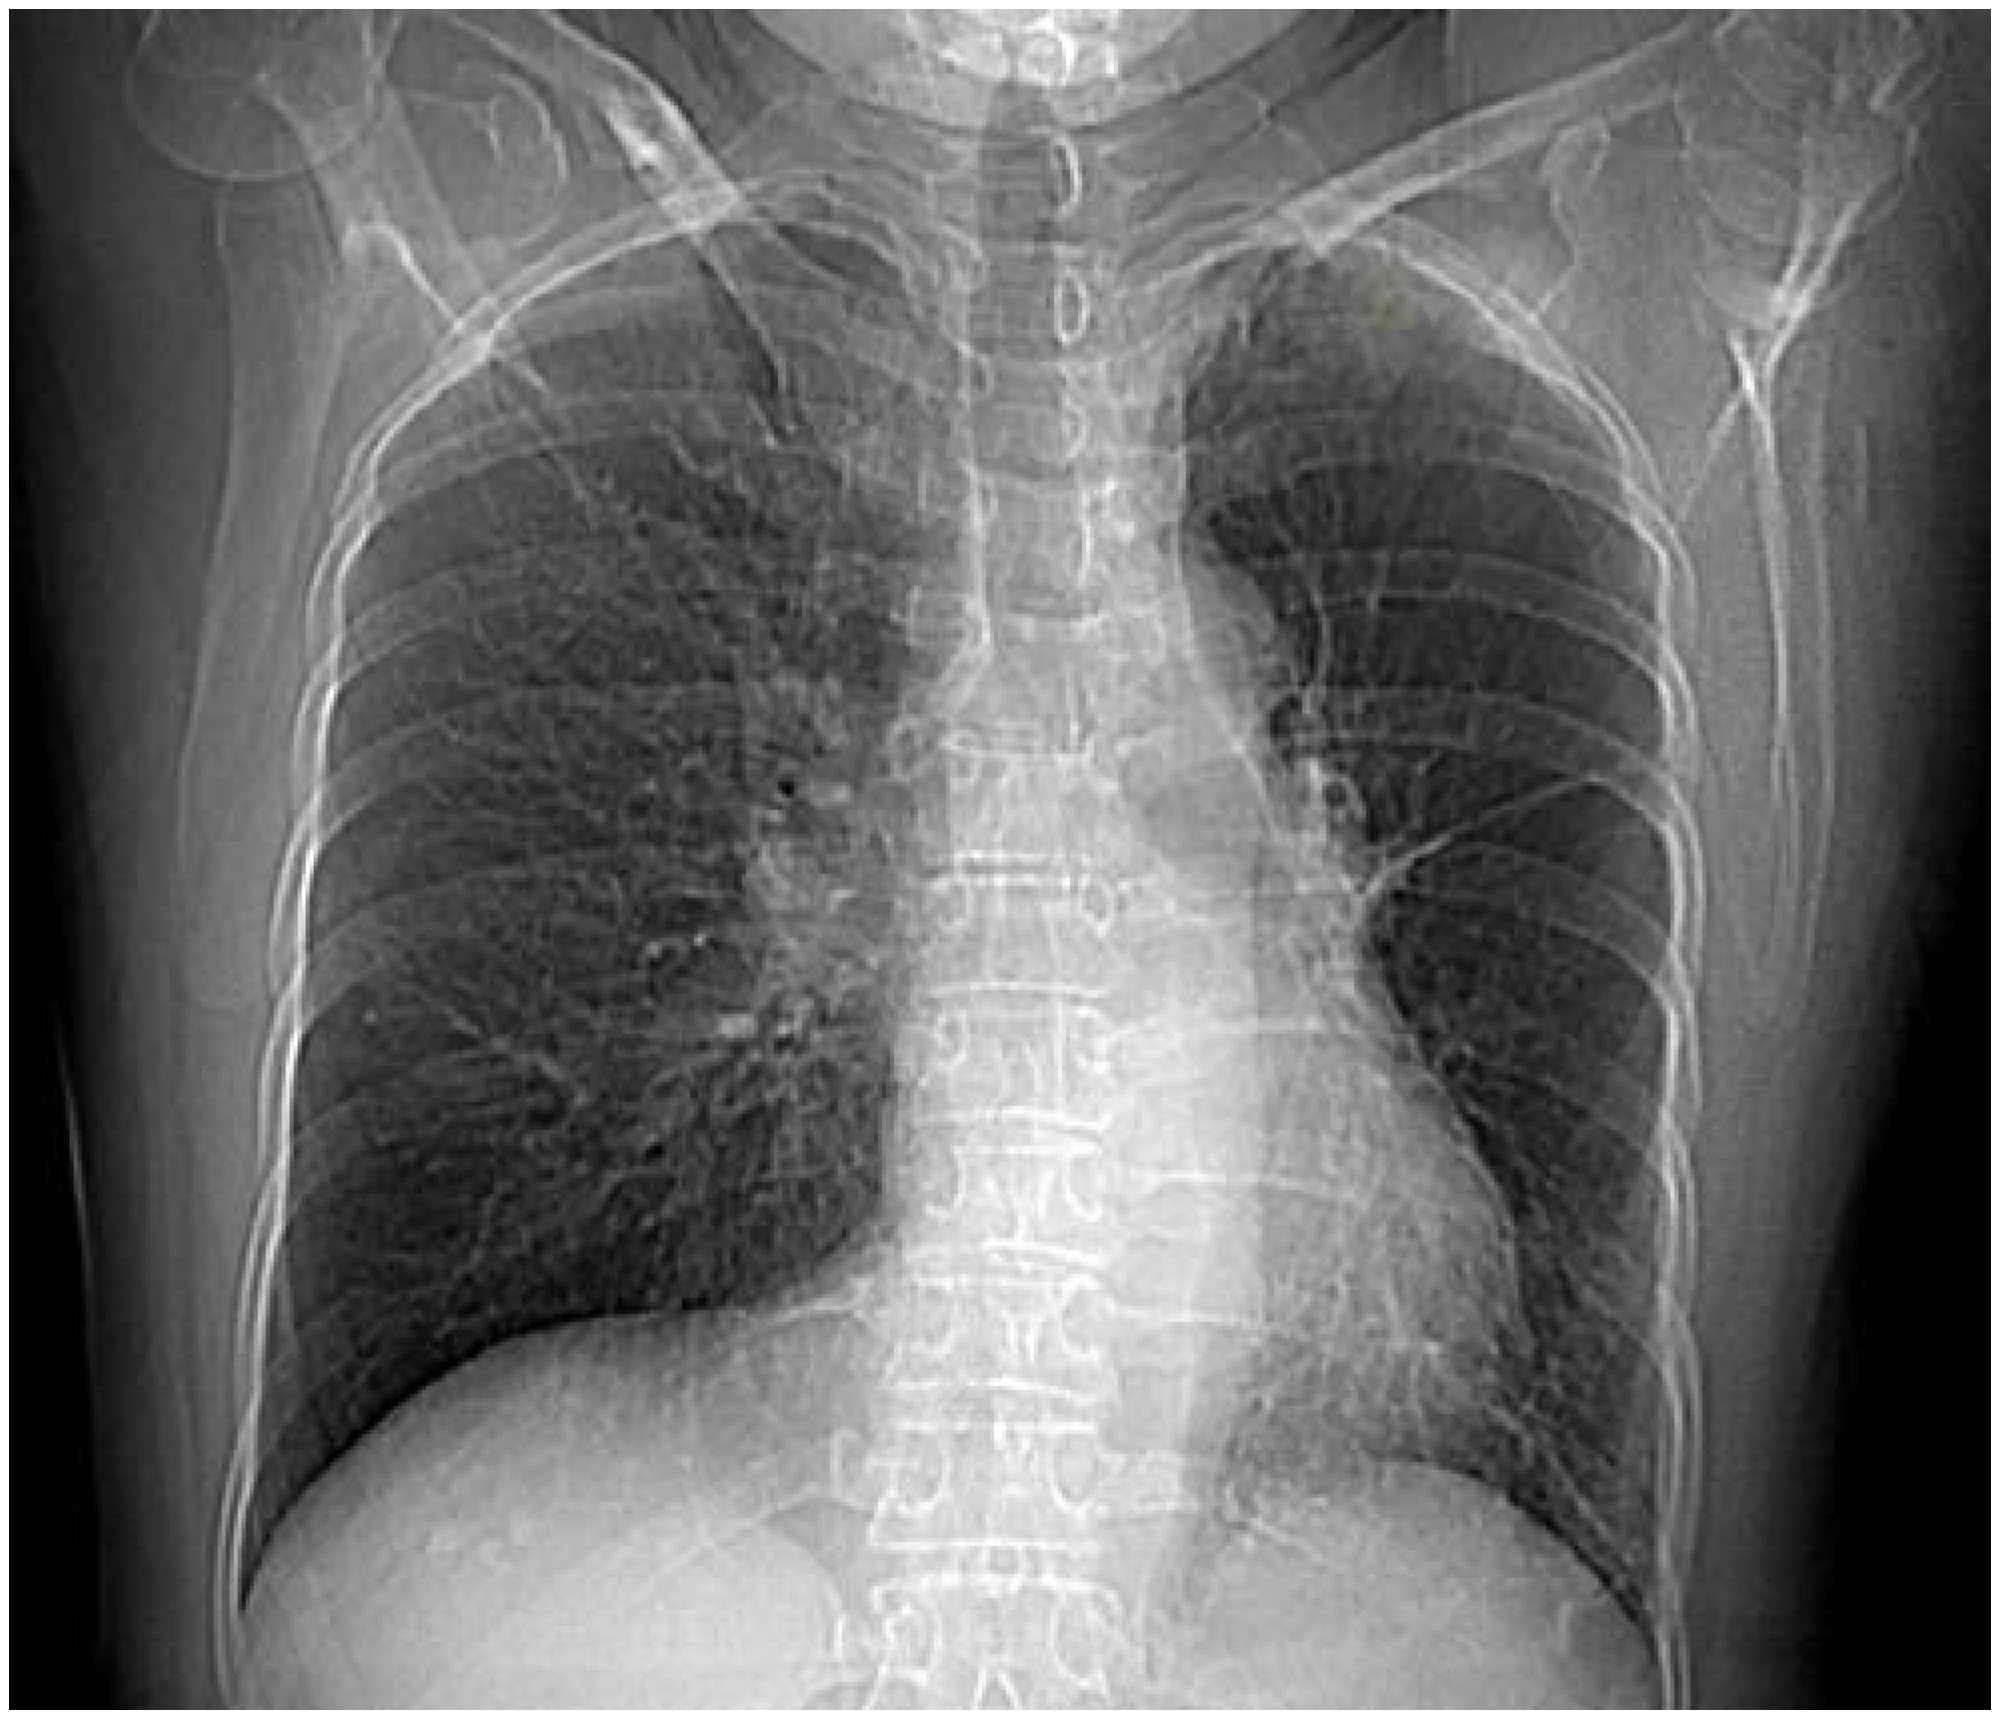

Chest radiography showed slight mediastinum shift to the left, pleuropericardial adhesion on the left, sequelae of TB with no signs of acute infection (Figure 1).

Heart electrocardiogram is normal unless there is PHT when there is a right ventricular dominance [6].

Chest X-ray shows diminished ipsilateral hemithorax with hyperlucent lung. Ipsilateral hemidiaphragm is elevated and the mediastinum is shifted to the affected side with insufficient or missing hilum and hyperinflation of collateral lung [6,7].

Figure 1. Chest X-ray showing slight mediastinum shift to the left, pleuropericardial adhesion on the left, diminished left hilum, hyperlucent left lung.